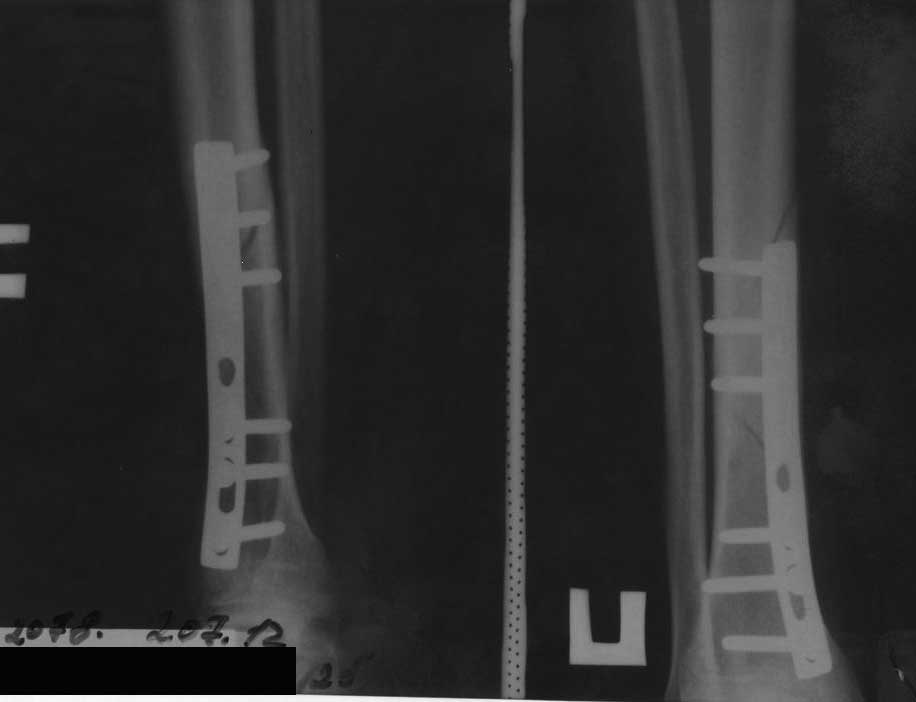

[Ortho] Повторный перелом н/3 большеберцовой кости с наличием металлофиксаторов

Больной 25 лет, нормостеник, курящий. Травма бытовая 28.01.2012. Госпитализирован в травм. отделение. 30.01.2012 выполнено оперативное вмешательство - открытая репозиция, металлоостеосинтез накостной пластиной (сразу приношу извинения за качество п/о рентгенограмм, к тому же, у больного сохранился

снимок только в прямой проекции). П/о период без особенностей. Выписан на амбулаторное лечение. Через 4 месяца - полная нагрузка на ногу, вёл обычный образ жизни. 02.07.2012 спрыгнул с дерева и внезапно почувствовал сильную боль в голени. На рентгенограмме - повторный перелом. Временно наложен сапожок HM Cast. Вопрос: что делать? Оставить так как есть? Открыться и поставить пластину подлиннее(на б/б стержень у больного нет $)? По-моему, линия излома проходит через места выхода винтов, боюсь, как бы они не стали "распоркой" для костных отломков и не стали препятствовать сращению... Заранее благодарен за помощь.